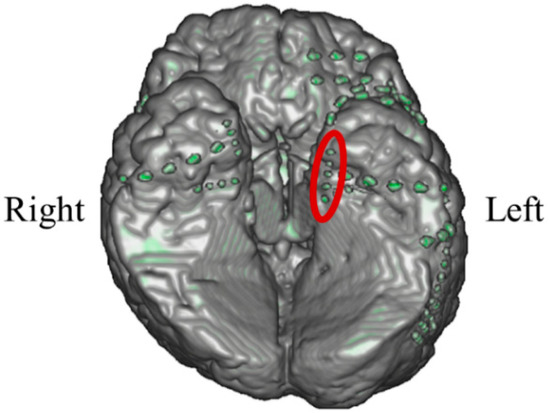

In P01, deep electrodes (Unique Medical, Tokyo, Japan) were implanted in the right MTL. The iEEG data were measured from four platinum electrodes (1 mm in length), positioned at 5 mm intervals (centre to centre) from the tip located in the right hippocampus, and used for NF (Figure 4). A reference electrode was placed subcutaneously on the right side for P01.